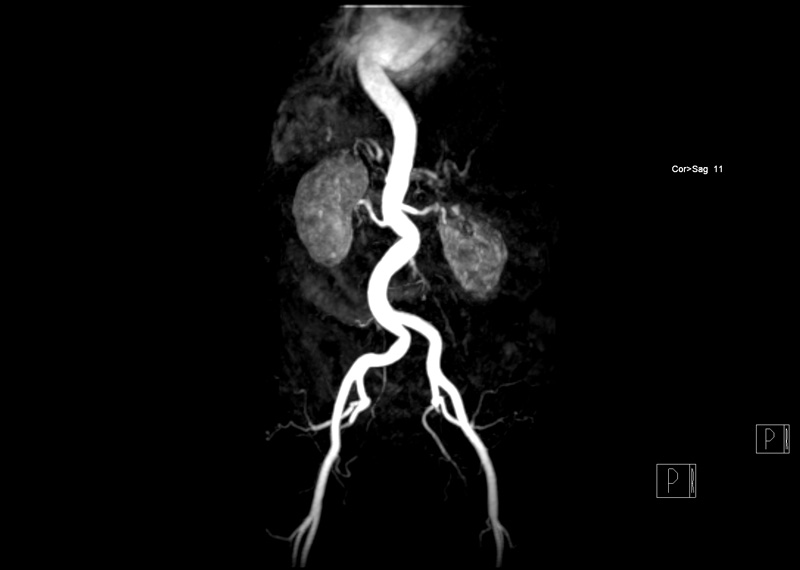

Die Magnetresonanztomographie (MRT), auch Kernspintomographie, ist ein faszinierendes bildgebendes Verfahren, mit dem man auf einfache Weise ins Körperinnere sehen kann.

Die MRT-Technik benutzt keine Röntgenstrahlung, sie arbeitet mit Magnetfeldern und Radiowellen. Sie ist somit gesundheitlich unbedenklich. Hierdurch werden außergewöhnlich detaillierte Bilder des Körpers möglich. Sie eignet sich durch ihre Genauigkeit und Zuverlässigkeit hervorragend sowohl im Bereich der Vorsorge als auch zur Abklärung vieler Fragestellungen.

Die Bilder sind hochauflösend und in 3D darstellbar. Aussagekräftige Aufnahmen erlauben es, gesundes von krankem Gewebe unterscheiden zu können. Diese Methode hilft oft dort weiter, wo andere Methoden keine zuverlässigen Ergebnisse liefern.